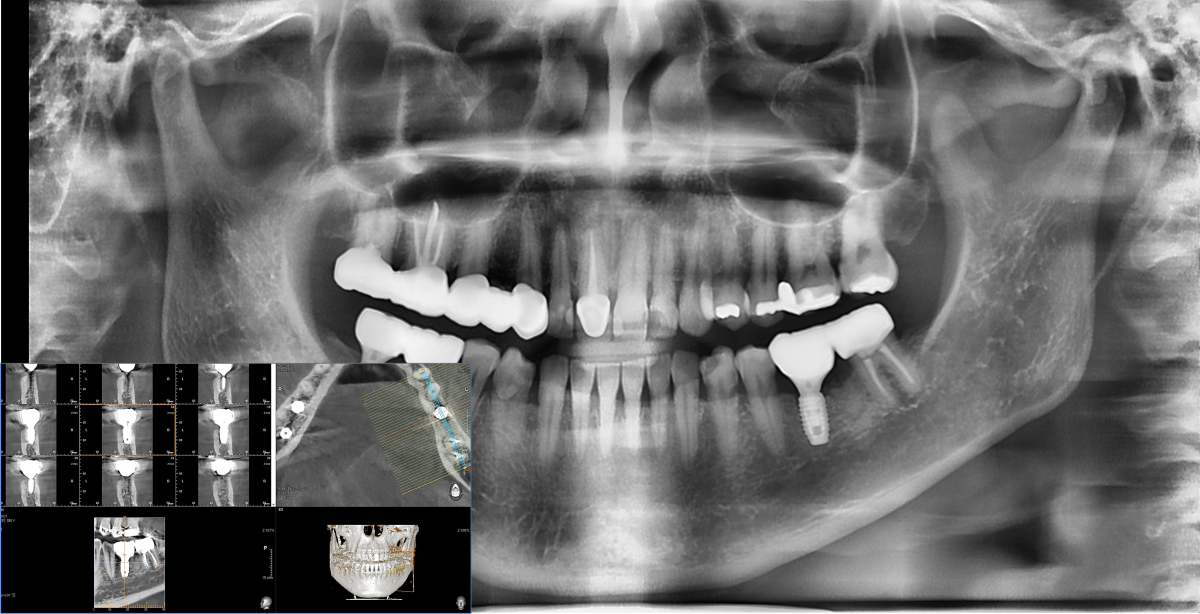

Immediate placement of an implant (Arum Dnetistry NB1, 5*8.5)

Immediate placement of an implant

A 51-year-old patient complained of an

old-crowned molar. The lower left molar had a gold crown, and the margin showed discoloration indicative of inner caries. Also, it had furcation-involved periodontitis

with an apical lesion.

Extraction and immediate placement of an implant.

▲Arum Dentistry NB1 fixture (5*8.5mm)